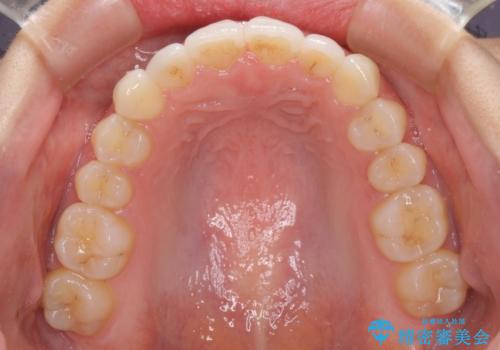

口が閉じにくい 1本飛び出した前歯の矯正治療

- 1本飛び出した前歯を治したいとのことで来院された患者様です。

歯列全体の拡大とIPR(歯と歯の間を削る)によってデコボコが解消するようにし、さらにゴムかけを活用して右側の咬み合わせ位置を変えるように設計し、インビザラインにより治療を行うこととしました。

結婚式までに前歯を整えたいとのことでしたが、インビザラインでは先に奥歯を移動させてから前歯を動かすため、間に合わない可能性がありました。しかし、結婚式までに期間があったことと、マウスピースをしっかりと装着してくださったことで、十分な歯列に整えることができました。

楽しく通院していただき、辛いと思っていた治療もあっという間であったそうで、患者様には大変満足していただきました。